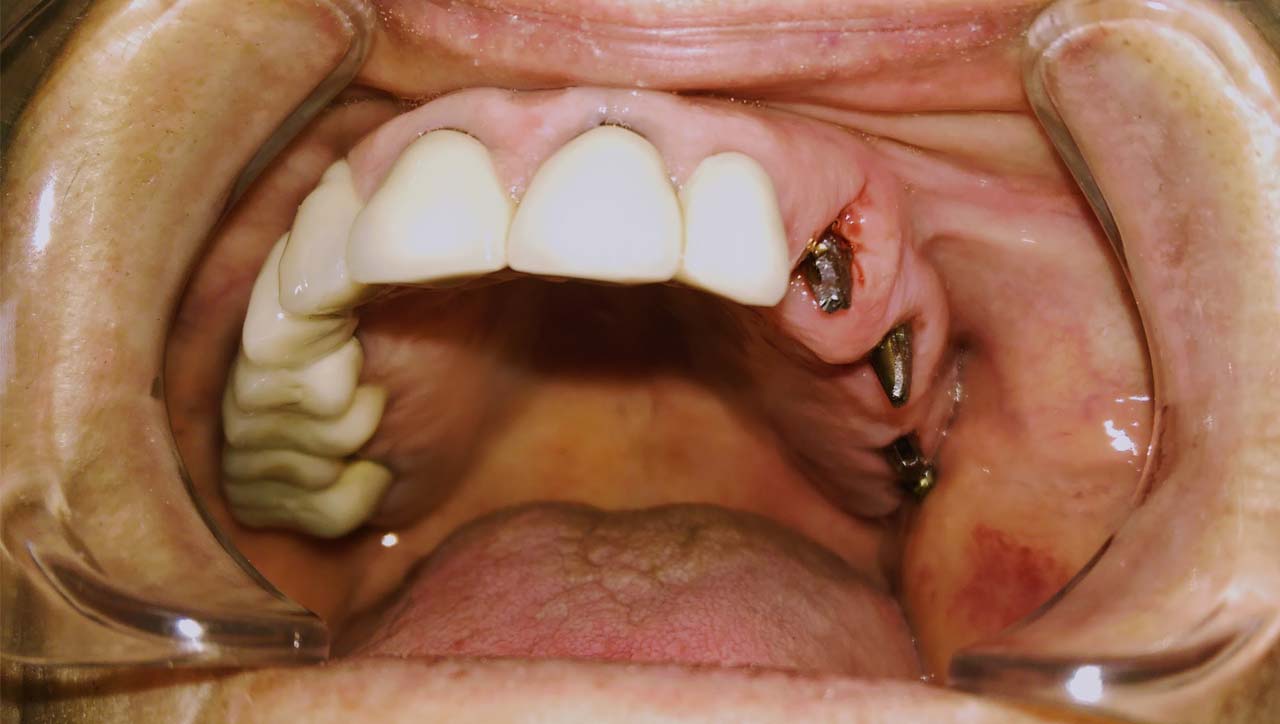

A mozgó, törött fogakon álló hidat a fogakkal együtt eltávolítottuk.

A fogak helyére, és a stratégiailag jó csontállományú hátsó területre azonnal behelyezett implantátumokra 3 nap múlva elkészítettük az esztétikus, azonnal terhelhető ideiglenes hidat.

Esztétikus Implantáció